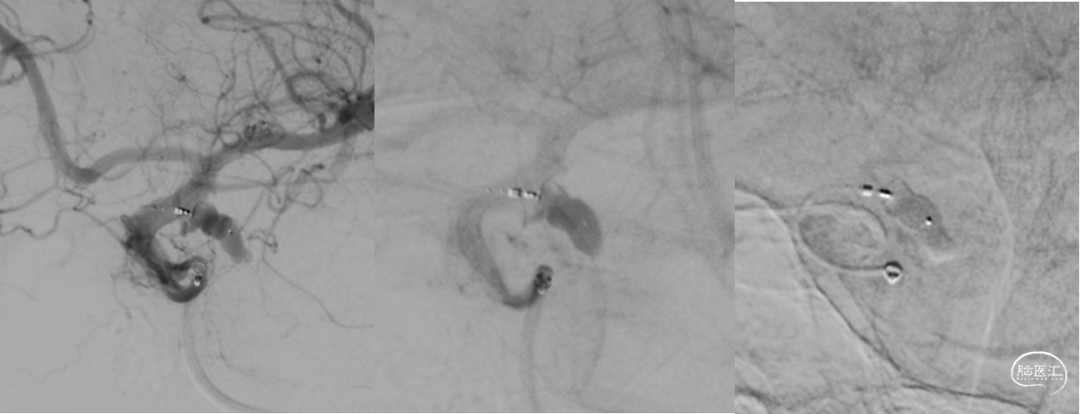

DSA

平均宽度(4.5+3.8)=4.2mm,最小深度7.5mm,选择SL5x3

微导管到位动脉瘤腔

通过VIA17释放web

造影可见造影剂滞留

手推造影-推挤-造影

解脱web

术后正侧位造影

术后CBCT